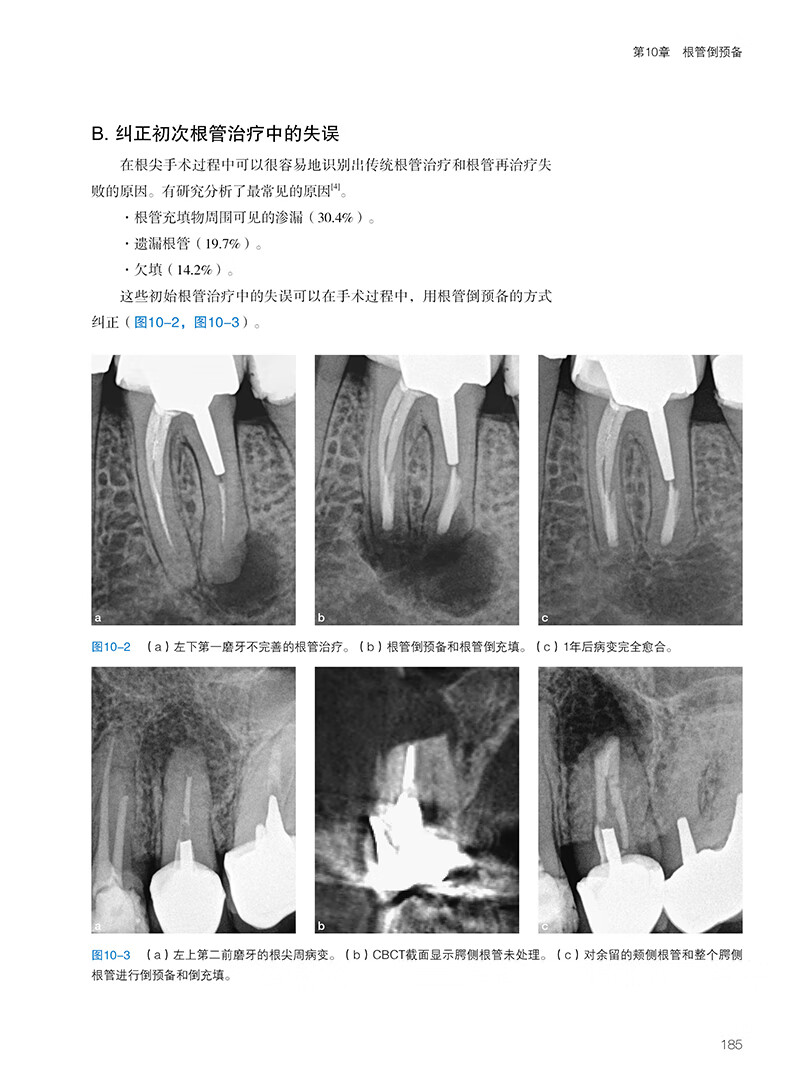

影像失真